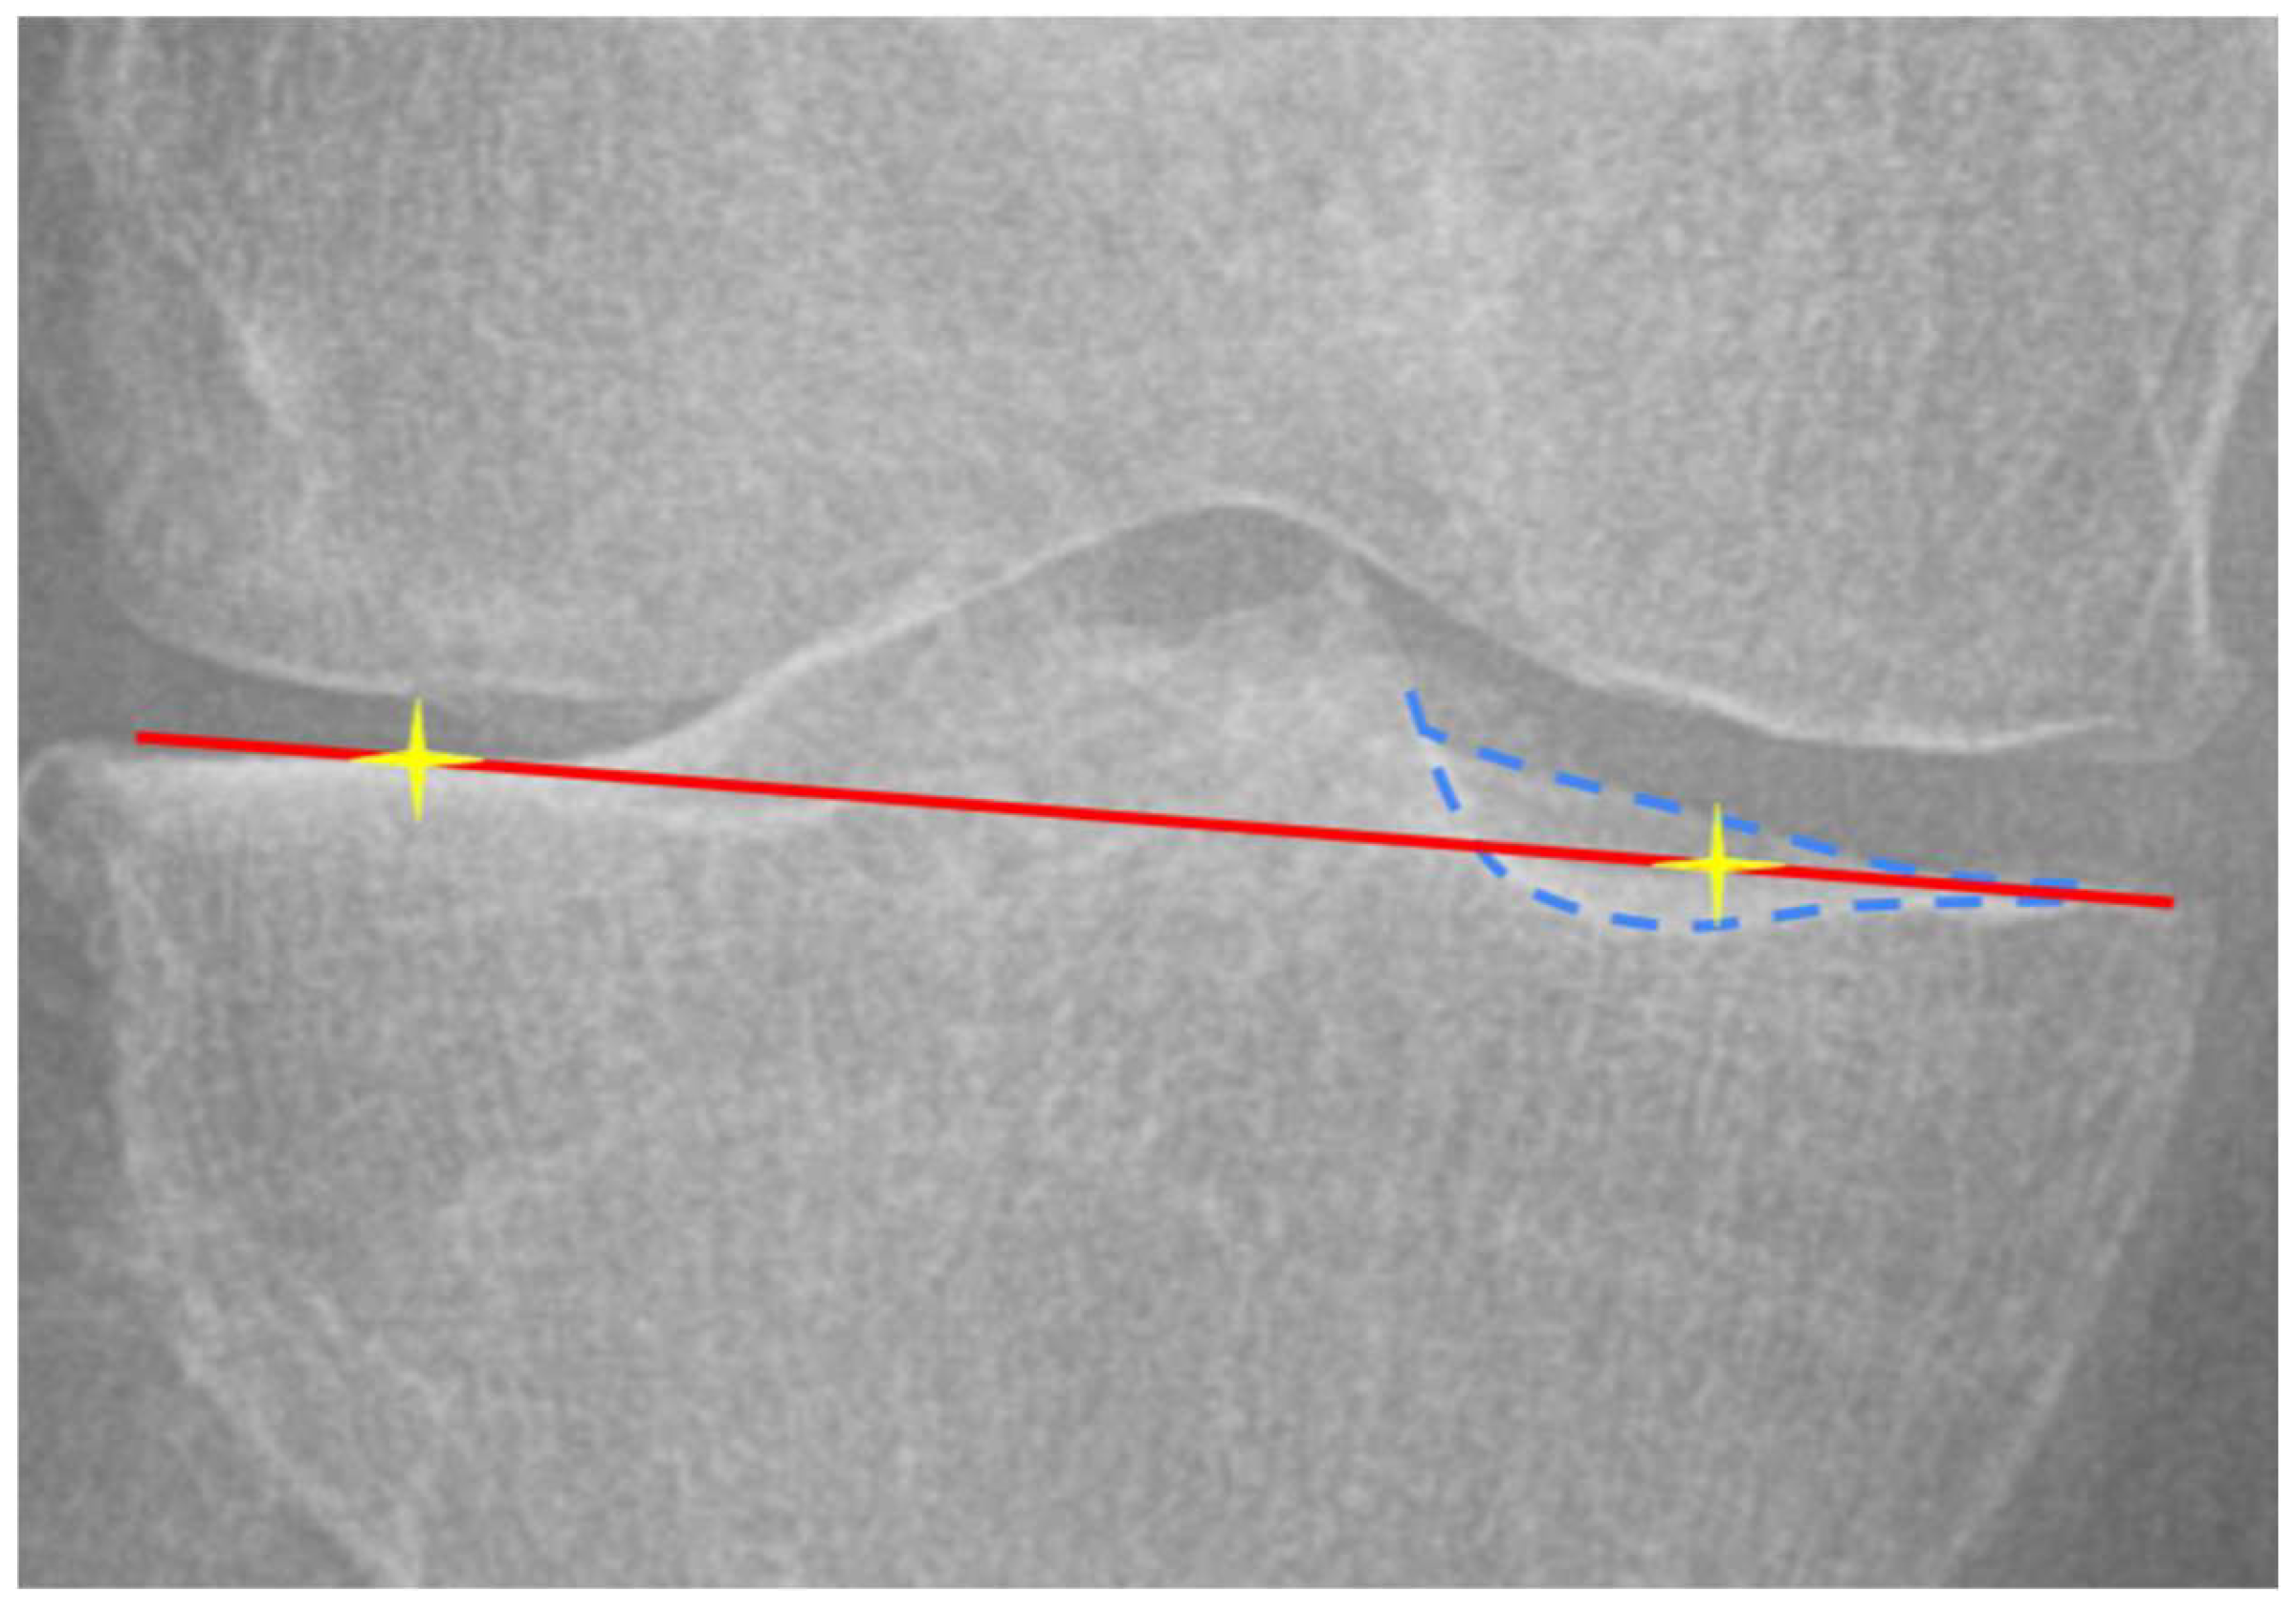

2.3. Landmark Definition and Measurement

| FNPR | femoral notch projection ratio index |

| PPR | patellar projection ratio index |